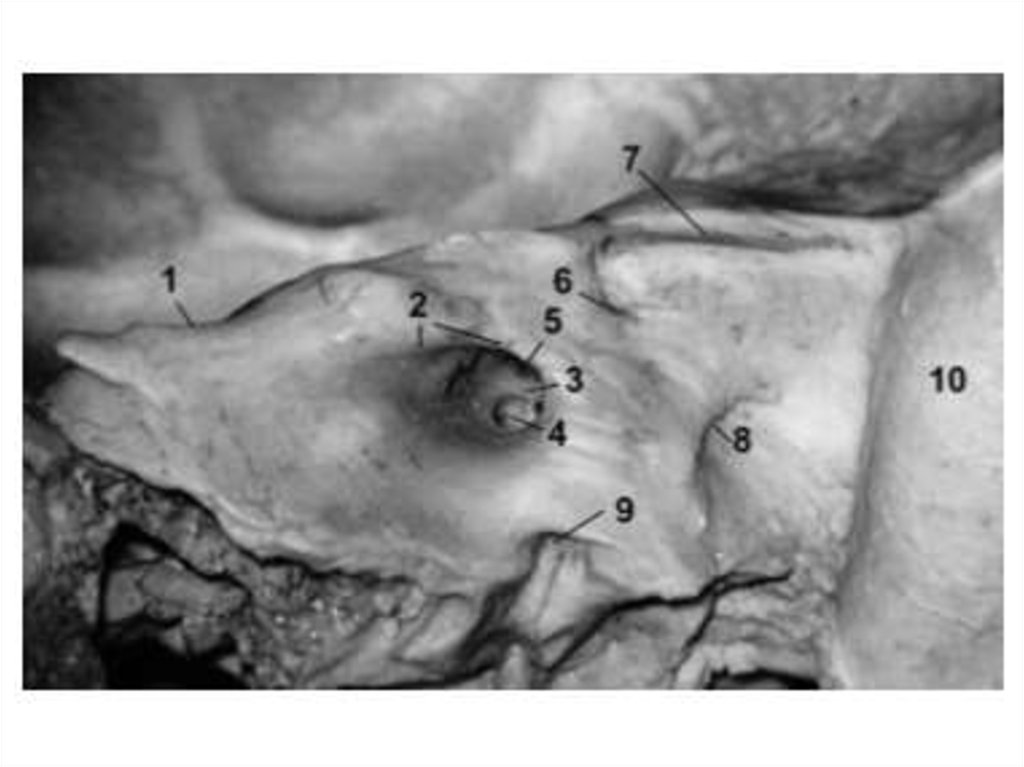

ЗРИТЕЛЬНЫЙ КАНАЛ

Проходит через основание малого крыла и соединяет

СЧЯ с глазницей.

Стенки:

• Внутренняя стенка – тело клиновидной кости;

• Верхняя стенка – передняя ножка малого крыла;

• Латеральная и нижняя стенки – задняя ножка малого

крыла.

Содержимое:

• Зрительный нерв;

• Глазная артерия.

ПРЕДПЕРЕКРЕСТНАЯ БОРОЗДА

Проходит горизонтально между внутренними отверстиями

зрительных каналов

ВЕРХНЯЯ ГЛАЗНИЧНАЯ ЩЕЛЬ

Ограничена:

• Сверху и медиально – задний край малого крыла;

• Снизу – лобный край большого крыла.

СЧЯ глазница

• глазодвигательный, блоковый, отводящий, глазной нервы;

• добавочная ветвь средней менингеальной артерии.

Глазница

СЧЯ

• верхняя глазная вена.

КРУГЛОЕ ОТВЕРСТИЕ

• верхнечелюстной нерв;

• венозное сплетение.